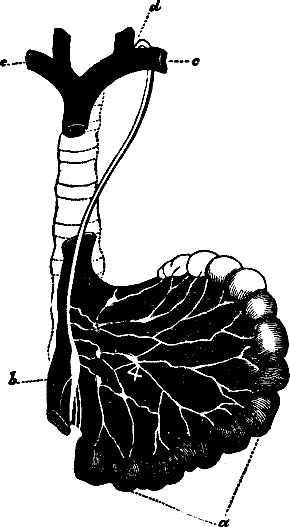

Fig. 29. Small and large intestines. 1, 1, 2, 2. Small intestine.

3. Its termination in the large intestine. 4. Appendix

vermiformis. 5. Cæcum. 6. Ascending colon. 7.

Transverse colon. 8. Descending colon. 9. Sigmoid flexure of

colon. 10. Rectum.